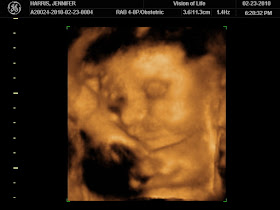

This afternoon we had our 3D/4D ultrasound for baby H #2! We went to the same place as we did with Austin and at 30 weeks just like we did with Austin....BUT this baby didn't quite cooperate the way Austin did...

The tech said baby had enough room in there but for some reason he wanted to be curled up in a little ball the ENTIRE time! From what we saw, he looks a lot like his big brother, but it was kind of hard to get the greatest pictures because he had his little knees in his face the whole time.

But for now, enjoy the cute pictures of our sweet nameless little boy...I especially love the one of his little ear!

A perfect little ear shot!